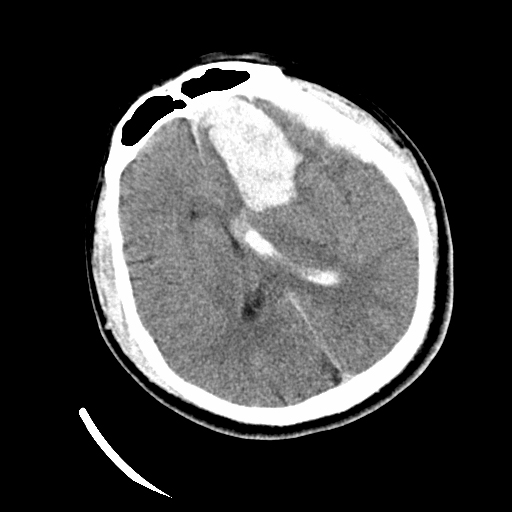

25岁的男青年小董,在2024年4月的一天,无明显诱因突发剧烈头痛后很快进入昏迷状态,就诊于首都医科大学附属北京潞河医院急诊神经外科,头颅CT检查显示:左侧额叶大量出血。入院后,急诊进行脑血管造影,发现左侧颅底的硬脑膜动静脉瘘,颅底脑膜广泛供血。考虑到硬脑膜动静脉瘘导致大量出血,病情复杂,且双侧瞳孔散大,脑疝形成。王浩主任医师、杨俊副主任医师迅速判断病情后,认为需要急诊行开颅探查血肿清除去骨瓣减压术+硬脑膜动静脉瘘切除术。在麻醉科的积极配合下,手术团队成功清除脑内血肿,术中发现硬脑膜动静脉瘘复杂予以切除,同时行去骨瓣减压术,解除脑疝,手术历时6个小时,最终顺利结束。小董被平稳转运回重症监护病房,术后经过科室医护团队的精心治疗与护理,小董出院了。出院时小董神清语利,双侧肢体肌力正常,无明显神经功能障碍,生活完全自理,出院前进行CTA评估硬脑膜动静脉瘘有部分残留,拟3个月后回医院进行颅骨修补手术时一并切除。

急诊手术前